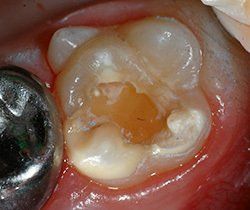

Bei Substanzdefekten, Karies und starker Empfindlichkeit sind Compositefüllungen und eventuell stützende Edelstahlbänder die beste Versorgung. Hier ein Fall aus unserer Praxis:

Passendes Molarenband vor dem Eingliedern

Fertig eingegliedertes Molarenband